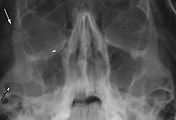

외안근외안근

TAO 시 외안근의 비대가 발생하게되는데, 뚱뚱해진 근육이 수축은 할수 있으나, 이완되지 못하는 "제한사시"를 보여 이로 인해서 복시가 발생합니다.

안구운동장애와 복시안구운동장애와 복시

임상적으로 정면 주시시보다 상방주시시 안압상승이 4mmHg 이상 나타나면 하직근의 제한사시가 있다고 의심합니다.